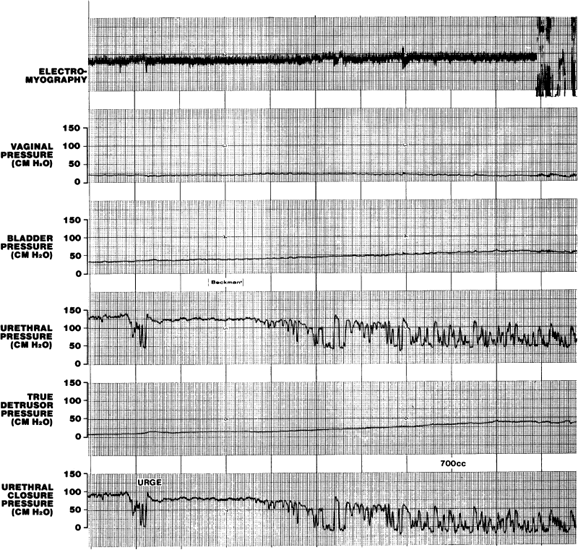

The performance of urethrocystometry involves the use of pressure-measuring catheters and transducers that are placed in the urethra, bladder, and rectum or vagina to measure intra-abdominal pressure.96–98 Analog or digital urodynamic monitors are used to measure these three pressures and the true detrusor pressure from instantaneous subtraction of abdominal from bladder pressure and urethral closure pressure that is calculated by subtraction of bladder pressure from urethral pressure. Measurement of these five pressures with or without electromyography (EMG) can be accomplished during filling to create an urethrocystometry study (Fig. 5).90 Urethral and bladder pressures can be measured by the same microtransducer catheter. This also can be used to fill the bladder through a small infusion channel in the center of the catheter (Fig. 6). Patients are positioned on birthing chairs, x-ray tables, or urodynamic commode chairs, and a single transducer catheter is placed in either the vagina or rectum to measure the intra-abdominal pressure. The dual transducer catheter is placed in the urethra and positioned so that the proximal microtransducer, which is 6 cm from the catheter tip and distal transducer, is placed at the point of maximal urethral pressure and oriented laterally. Filling is then begun in a retrograde fashion either through the lumen of the urethral catheter or via a separate small catheter or pediatric feeding tube.96 Cystometric parameters and changes are noted as described previously with subtracted cystometry, but urethrocystometry offers the added advantage of being able to monitor urethral pressure.

Fig. 5. A urethrocystometry study in a 32-year-old woman with urinary urgency and frequency, demonstrating urethral instability (marked variation in urethral pressure) without any detrusor instability.

Monitoring urethral pressure during cystometry is advantageous because it allows the detection of urethral pressure decreases that normally occur before a bladder contraction, whether voluntary or involuntary, and such variations usually are associated with corresponding EMG changes. Alternatively, one may observe marked variations in urethral pressure without detrusor contractions. This urethral instability may be a forerunner of detrusor instability (Fig. 7) and often signifies an impending bladder contraction.99–101 These pressure variations may be associated independently with symptoms of urgency and sensory urge incontinence.99,100 Some investigators question, however, whether these pressure fluctuations have any significance at all.102 Exaggerated urethral pressure fluctuations may be directly associated with complete urethral relaxation and may cause urinary incontinence from uninhibited urethral relaxation.11 Care must be taken to ensure that these urethral pressure variations are not artificial (i.e. due to patient movement, abdominal pressure changes, voluntary contraction of the levator ani muscles). Alpha blockers may relieve symptoms in some patients with urethral instability. Urethral pressure decreases preceding detrusor instability can be used as a marker for biofeedback therapy to train patients to inhibit involuntary detrusor contractions. In healthy women, filling the bladder will lead to a rise in urethral pressure secondary to increased skeletal muscle activity associated with a gradual increase in skeletal muscle EMG activity (augmentation). This may be triggered by stretch receptors in the bladder trigone.103

Fig. 7. An episode of urethral instability associated with urgency is a precursor of further intermittent urethral relaxation associated with an involuntary detrusor contraction at a maximum cystometric capacity of 700 mL.